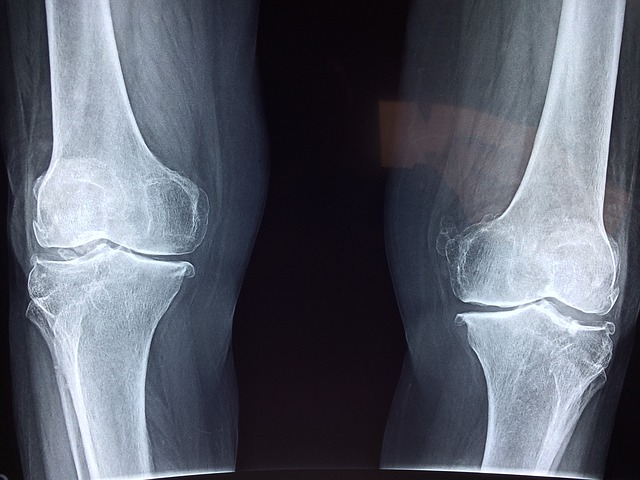

Kĺby sú v našom tele veľmi dôležité. Táto veta je asi zbytočná, však? O jej pravdivosti, však asi nikto nepochybuje. Bez kĺbov, by sa nám jednoducho žilo veľmi ťažko. Zároveň však patria k častiam tela, ktoré dostávajú najviac zabrať. Ak teda chcete, aby ste so svojimi vlastný kĺbmi dožili život, je potrebné sa o nich patrične postarať.

Každý kĺb potrebuje pre správne fungovanie zdravé chrupavky. Tie zas potrebujú kolagén. Ak teda chcete, aby bolo všetko v poriadku, musíte svojmu telu dodávať čo najviac tejto látky. Je síce pravdou, že telo kolagén produkuje aj samé. Vekom sa však jeho produkcia výrazne znižuje, v čoho dôsledku nastupujú problémy s kĺbmi. V tomto smere sú najlepšou voľbou výživové doplnky.